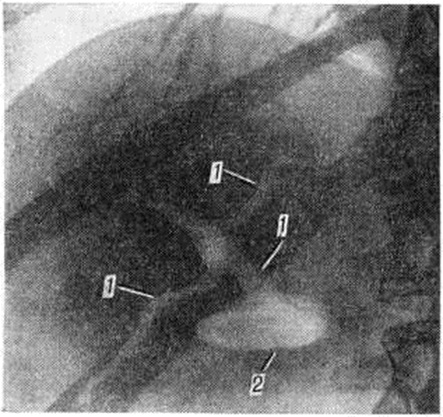

Внутренние Жёлчные свищи легко диагностируются при появлении примеси желчи там, где она в норме не бывает, например, примесь желчи к мокроте при образовании желчно-бронхиальных свищей. Но основным методом, позволяющим установить наличие внутреннего Жёлчные свищи и его локализацию, является рентгенологическое исследование — обзорная рентгеноскопия и рентгенография области печени и желчных путей (рисунок 3), при которых может определяться газ в желчных путях, дуоденография в состоянии искусственной гипотонии (смотри полный свод знаний Дуоденография релаксационная); при желчно-бронхиальных свищах диагноз облегчает бронхография (смотри полный свод знаний). Внутривенная холангиография не всегда выявляет внутренний Жёлчные свищи, так как сброс контрастного вещества через широкое свищевое отверстие препятствует концентрации его в желчных протоках (смотри полный свод знаний Холеграфия). Позволяет уточнить характер и локализацию.

Жёлчные свищи холангиография на операционном столе (смотри полный свод знаний Холангиография).

Рисунок 3. | ||